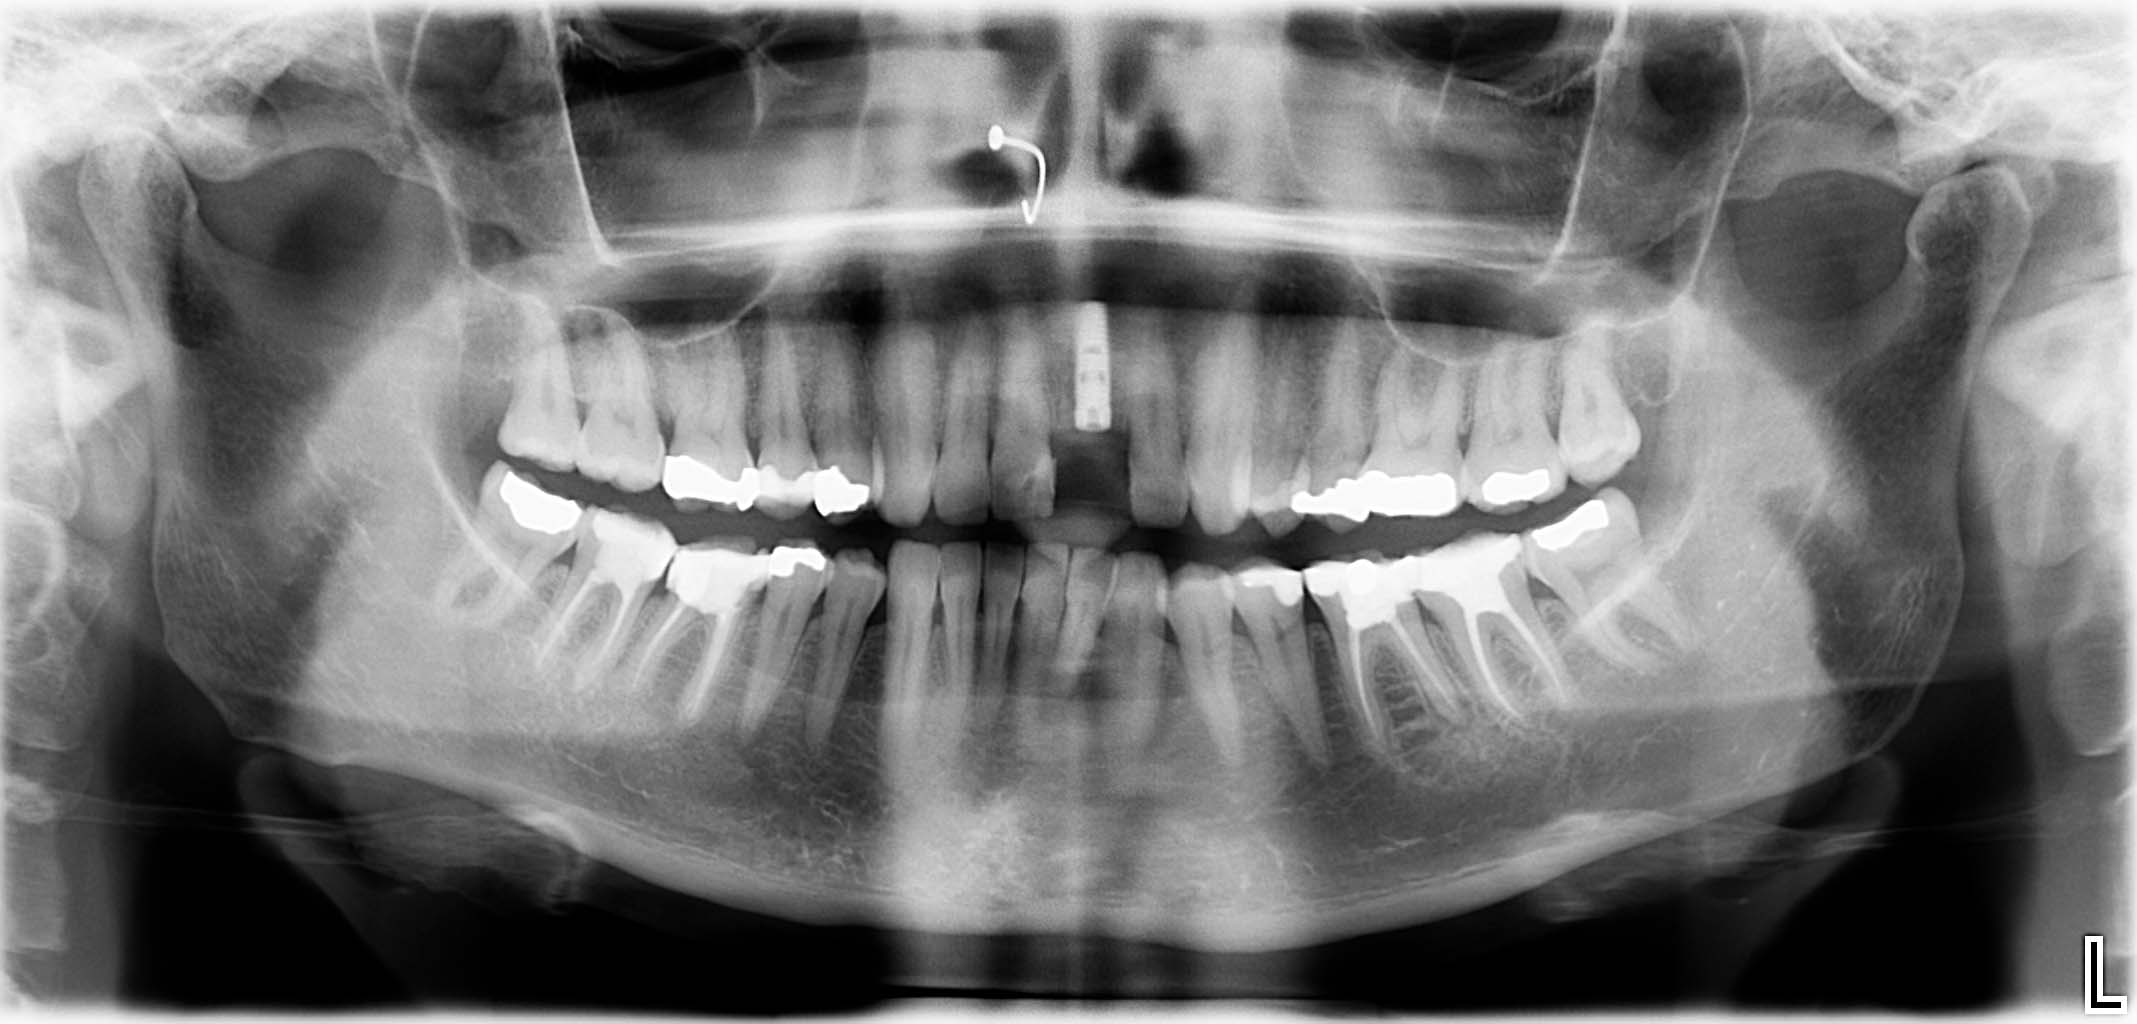

Ausgangssituation: Zahn 36 mit apikaler Beherdung, nicht erhaltungswürdig